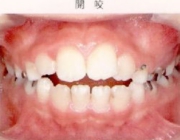

●開咬

奥歯の数本だけが噛んで前歯が噛めない状態のことと言います。